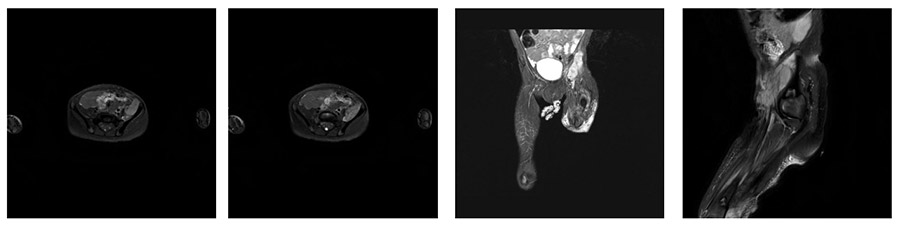

VAKA 2: Pelvis İçi Yerleşimli Rhabdomyosarkom

Karında ağrı ve şişlik nedeniyle başvuran hastamızın yapılan muayenesi ve radyolojik tetkiklerinde yumuşak doku kitlesi saptanması üzerine uygulanan iğne biyopsisinde yumuşak doku sarkomu (Rhabdomyosarkom) tanısı kondu. Kemoterapi ve radyoterapi sonrası mevcut tümör yapışık olduğu ana damarlar ile birlikte temiz sınırlar ile çıkarıldı ve sentetik greft ile bypass yapılarak ameliyat tamamlandı.

Ameliyat Öncesi: Sol hemipelvis yerleşimli eksternal iliak arter ve veni içine alan düzensiz sınırlı heterojen kitle görülmekte